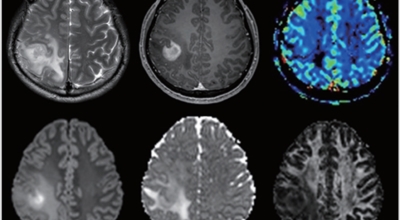

뇌종양이란 뇌 조직이나 뇌를 싸고 있는 막에서 발생한 종양과, 머리뼈나 주변 구조물로부터 멀리 떨어진 부위에서 뇌 조직이나 뇌막으로 전이된 종양을 의미해요. 뇌종양은 양성과 악성으로 나눌 수 있습니다. 양성 뇌종양은 성장 속도가 느리며 주위 조직과의 경계가 뚜렷해요. 양성 뇌종양은 수술 이외의 다른 치료 없이 완치되는 경우가 흔하고, 대부분 천천히 자라기 때문에 수술하지 않고 경과를 관찰하기도 해요. 그러나 양성 뇌종양도 완치될 수 없는 경우가 있습니다.

뇌간이나 척수와 같은 특정 부위에 발생된 종양은 수술로 없앨 수 없습니다. 또 크기가 작더라도 생명에 중요시되는 기능을 담당하는 뇌와 척수에 정도가 심한 훼손을 입힐 수 있답니다. 이 경우 조직학적으로는 양성이지만, 임상적으로는 악성과 같습니다. 악성 뇌종양은 뇌암이라고도 하고, 성장 속도가 빠르며 주위 조직으로의 침투 역량이 강해요. 이에 따라 정상 뇌 조직으로 침윤되고 정상 뇌 조직과의 경계가 불분명해서 치료가 어려운 편이예요. 악성 뇌종양은 주변의 정상 뇌 조직을 빠른 속도로 파괴해요.

뇌종양이 악성인 경우, 빨리 자라는 특성이 있기 때문에 수술적으로 절제가 필요할 수 있습니다. 하지만 수술로 종양이 완벽하게 제거가 어려운 경우, 수술 후에 방사선 치료와 항암치료를 추가적으로 시행되어요. 요즘 들어서 뇌조직의 훼손을 최소화하고 수술 흉터가 거의 남지 않는 방법으로 하는 치료인 감마나이프 방사선 수술이 있답니다. 이 방사선 수술은 전신 마취와 피부 절개가 필요 없으며, 합병증이나 후유증이 적은 것으로 알려져 있답니다.